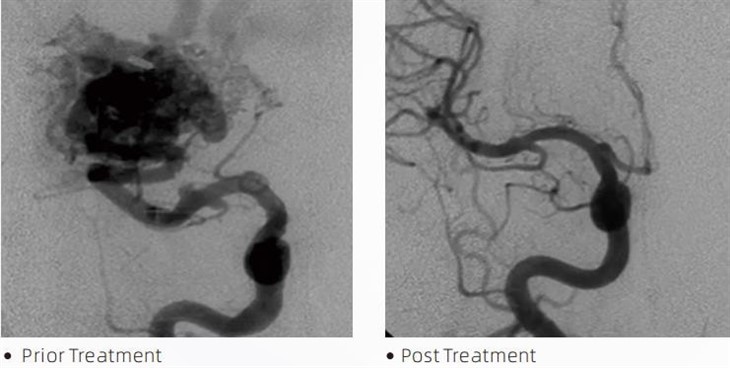

LavaTMembolische lijm is een medisch hulpmiddel dat door interventionele neuroradiologen wordt gebruikt tijdens minimaal invasieve procedures om aandoeningen zoals cerebrale aneurysma's, arterioveneuze misvormingen en tumoren te behandelen. De embolische lijm van Lava biedt zowel medische professionals als patiënten meerdere voordelen op het gebied van veiligheid, gebruiksgemak en effectiviteit. Lava is in staat bloedvaten snel en efficiënt af te sluiten. Het proces omvat het rechtstreeks injecteren van de lijm in het beoogde bloedvat, waar het polymeriseert en uithardt tot een gipsachtige massa die het aneurysma of de misvorming vult. Vervolgens wordt de bloedtoevoer naar de laesie effectief afgesneden, waardoor wordt voorkomen dat deze scheurt en het risico op blijvende schade of beroerte wordt verkleind. Lava omvat lava-12, lava-18 en lava-34. Elke formulering is ontworpen om aan specifieke klinische behoeften te voldoen. Lava-18 is een standaardformulering voor algemeen gebruik. Lava-34 is lijm met een hoge viscositeit voor vaten met een hoog debiet. Terwijl Lava-12 een lagere viscositeit heeft en beter vloeibaar is, waardoor distale microvaten mogelijk zijn. Met deze opties kunnen interventionele neuroradiologen de geschikte Lava-formuleringen kiezen om optimale resultaten te garanderen. Een van de meest opmerkelijke eigenschappen van Lava zijn de niet-klevende eigenschappen. Deze stof is speciaal samengesteld om stabiel te blijven totdat het het doelgebied bereikt. Deze eigenschap betekent dat lava-embolische lijm nauwkeurig in de slagader kan worden geplaatst en daar kan blijven zonder te kleven of te hechten aan het omringende weefsel.